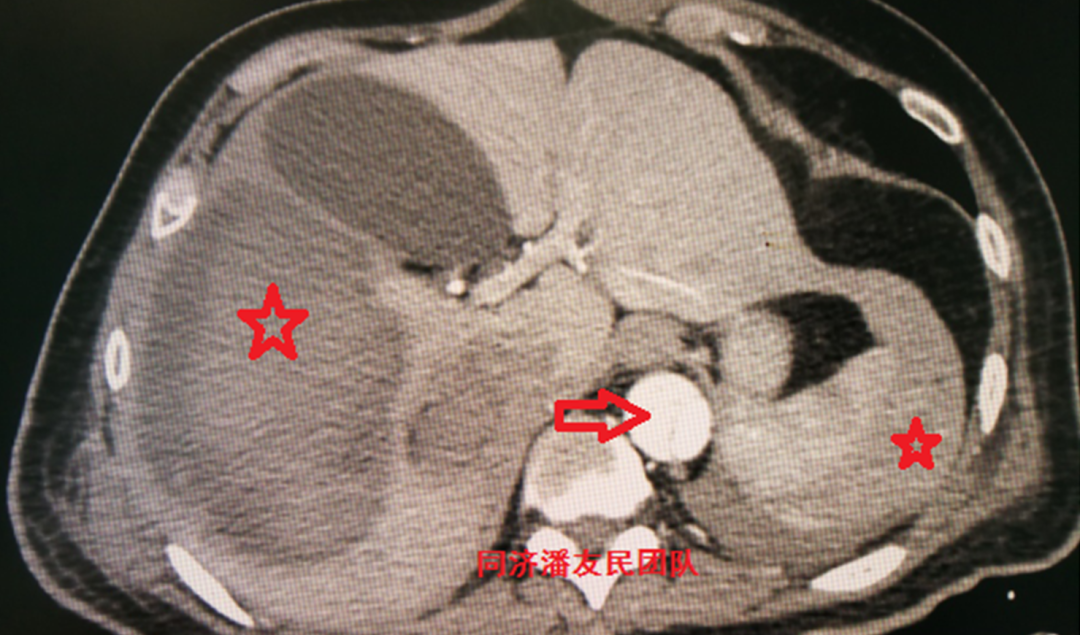

平扫ct显示腹主动脉段血管钙化点内移征(红箭头所示)

为腹主动脉 cta,可见腹主动脉内广泛的血栓/斑块状物质(红色箭头